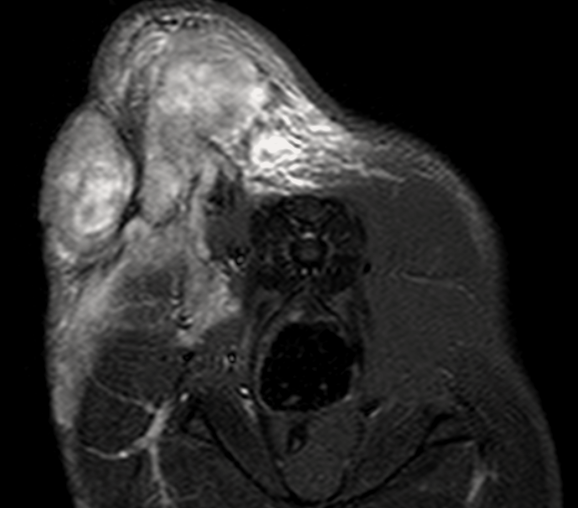

МРТ исследования проводятся на аппарате высокого качества Phillips Intera с напряженностью магнитного поля 1,5 Тесла. Позволяет максимально точно визуализировать анатомические структуры одинаково хорошо животному от 200г до 200кг

- Проведение мрт животному

- Подозрении на новообразование, когда установить диагноз другими методами невозможно.